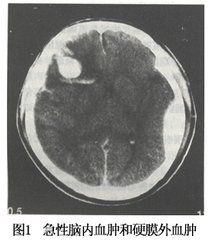

1.CT掃描

表現為圓形或不規則形均一高密度腫塊,CT值為50~90Hu,周圍有低密度水腫帶,伴有腦室池形態改變,中線結構移位等占位效應。常伴有腦挫裂傷及蛛網膜下腔出血的表現。